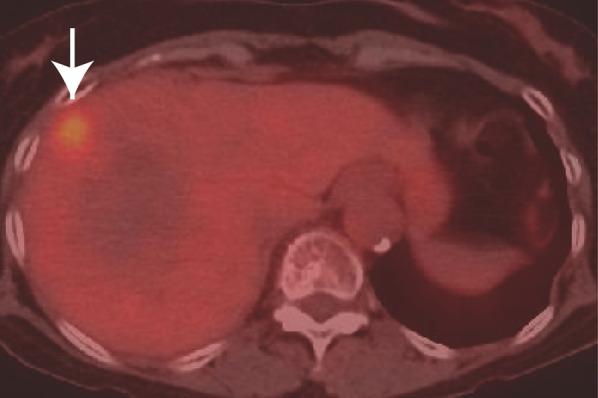

A 77-year-old woman who had undergone ileocecal resection for cecal cancer 5 years previously was found to have elevated levels of the tumor marker carbohydrate antigen 19-9. Although an abdominal computed tomography (CT) scan did not detect any liver mass lesions until 3 months before this serum examination, the subsequent CT scan revealed a hypodensity 20 mm mass lesion in the right anterior section. Contrast-enhanced CT and magnetic resonance imaging revealed peripheral enhancement in the arterial-to-equilibrium phase. Fluorodeoxyglucose positron emission tomography revealed uptake in the lesion. None of the imaging modalities showed lymph node swelling or distant metastases. She underwent hepatectomy under the diagnosis of ICC or an atypical metastasis from previous cecal cancer. Although preoperative images showed no suspicious lymph node metastasis 3 weeks prior, the hilar lymph node swelled 3 cm and contained adenocarcinoma. Consequently, the patient underwent right anterior sectionectomy and lymph node dissection of the hepatoduodenal ligament. Histopathological examination revealed that the liver tumor was a poorly differentiated adenocarcinoma with sarcomatous pattern. While the patient received adjuvant gemcitabine and S-1 therapy, lymph node metastasis appeared in the mediastinum 13 months after the surgery. She received gemcitabine + cisplatin + S-1 therapy but died 20 months after surgery.